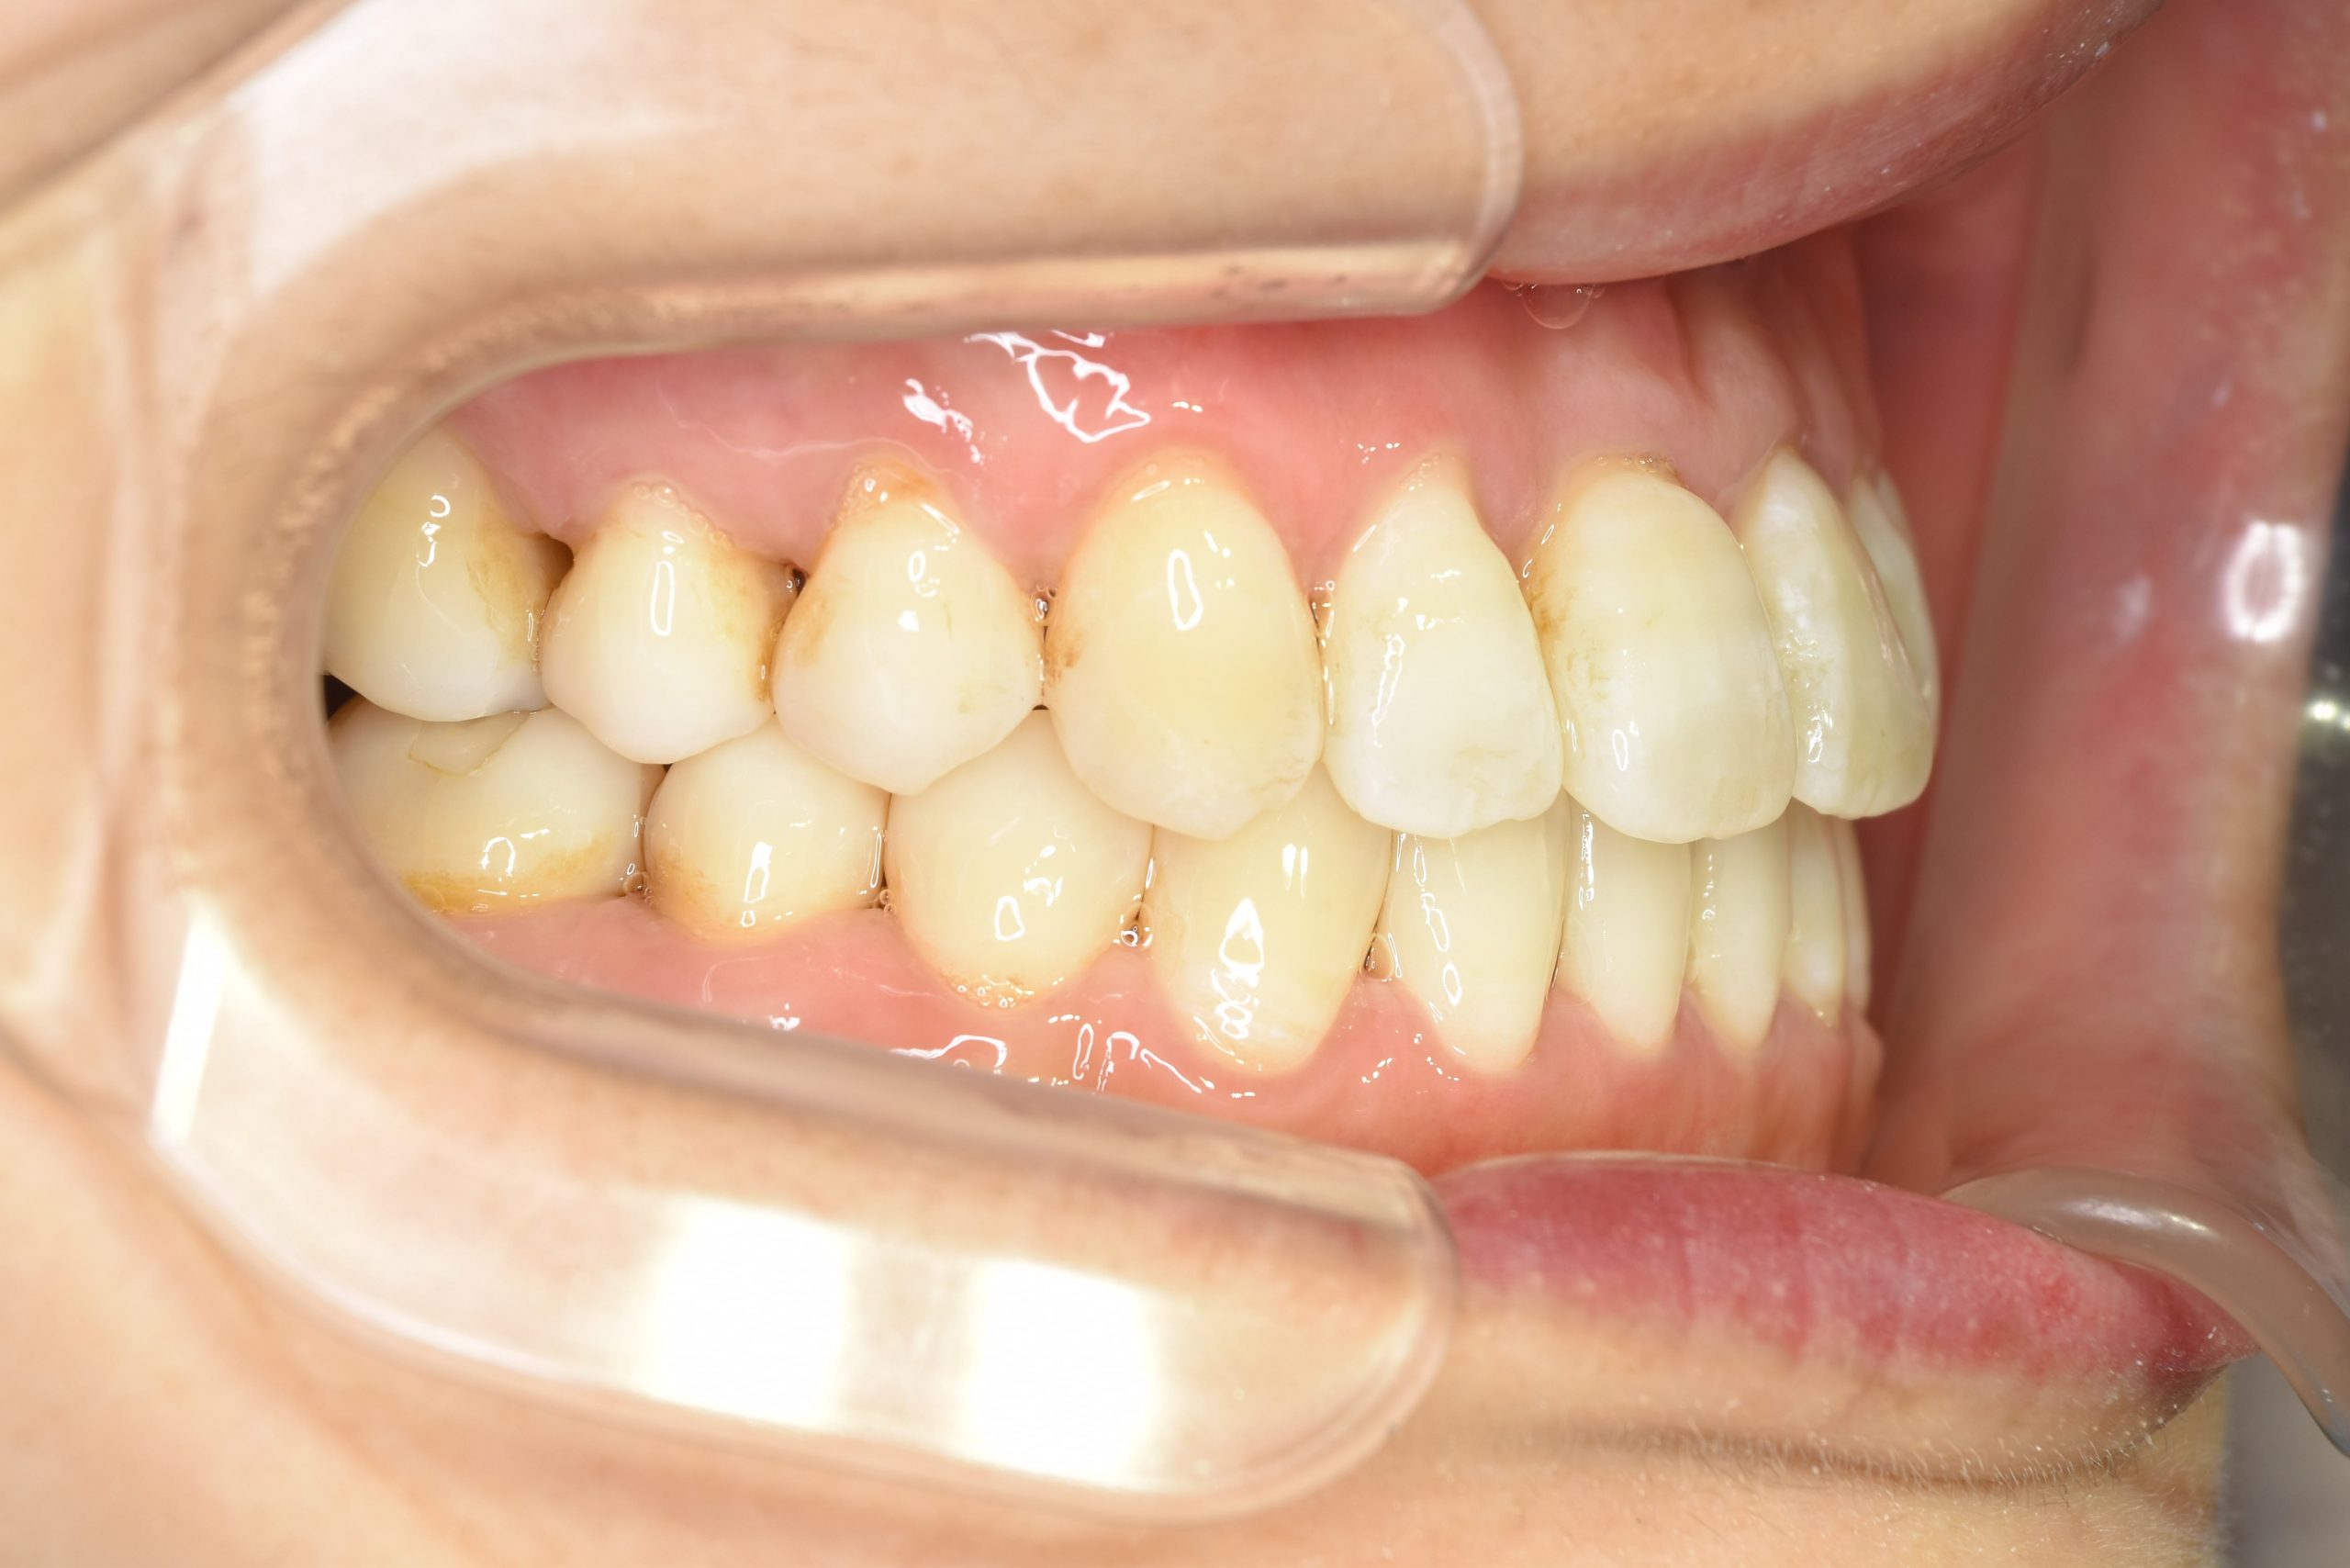

ビフォー

保険での矯正治療|症例_138

主訴 噛み合わせが悪い(反対)|歯並びが悪い|顎が出ている

施術内容 マルチブラケット装置を用いて歯牙を配列した後、

下顎骨離断術を行った。良好な咬合を獲得した。

治癒期間 3年8ヶ月間

費用 保険治療

リスク・副作用 違和感、不快感、痛み